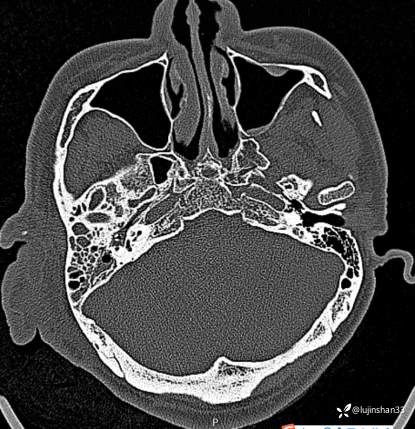

(2023-02-17 17:52,本院)行CT(血管心脏)检查提示:1、右侧耳颞部异常改变,考虑血管瘤可能,可见粗大供血动脉及引流静脉,局部动静脉瘘可能,右侧颈外动脉分支增粗,请结合临床及相关检查。2、左侧颈内动脉粥样硬化,管腔轻微狭窄,请结合临床。血管外科会诊意见:CTA示右颈外动脉起始部结扎后闭塞,介入栓塞暂无合适入路;

临床诊断:耳廓、颞骨蔓状血管瘤合并出血